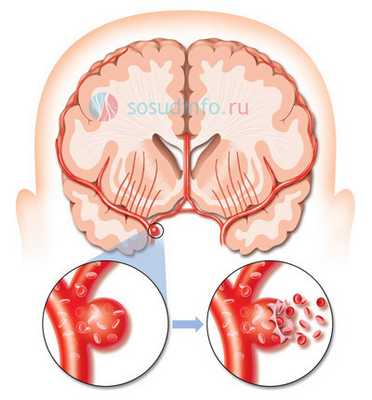

виды аневризм сосудов головного мозга

По размеру аневризмы бывают мелкими, средних размеров, крупными и гигантскими, одно- и многокамерными. В зависимости от локализации бывает аневризма сонной артерии (внутренней), передней и средней мозговых, вертебро-базилярного бассейна. Примерно 15% случаев составляют множественные сосудистые аномалии.

Из всех кровоизлияний внутри черепа субарахноидальное - одно из самых тяжелых, а причиной его в 85% случаев становится сосудистая мальформация. Кровь при этом проникает под мягкую мозговую оболочку, сдавливает мозг, нарушает движение ликвора, провоцирует тяжелые неврологические нарушения, а дислокация структур ствола мозга имеет высокий риск гибели в острейшем периоде заболевания.

разрыв аневризмы мозга

Аневризма - это патология, которая характеризуется расширением просвета сосуда, выпячиванием сосудистой стенки и формированием аневризматического мешка, обусловленная воздействием факторов врожденного или приобретенного характера. Как правило, аневризма развивается в стенке артерий, а не вен, и чаще всего локализуется в сосудах головного мозга и в аорте.

Аневризма головного мозга (АГМ) - это деформационные очень тонкие (по форме напоминают мешочки без характерной мускулатуры) выпячивания сосудов, как правило, в местах их разветвления или рядом. Проявляться они начинают на четвертом десятке жизни, несмотря на врожденное происхождение.

Диагностируются чаще всего между 30 и 50 годами. Разрыв такого образования при отсутствии лечения наблюдается примерно у половины больных, что приводит к кровоизлиянию в мозг и последующему летальному исходу (вероятность 50-65% в среднем).

По статистике заболевание встречается у 2-5% людей. После манифестации вероятность разрыва возрастает до 90%. Операция при аневризме сосудов головного мозга - единственный возможный способ устранения патологии и предупреждения повторного кровоизлияния.

Если объяснять простыми словами, то суть заболевания состоит в образовании очень тонких пузырьков из сосудистых стенок, которые легко лопаются. Патогенез заключается прежде всего в наследственной патологии, ее усугубляют высокое давление, холестериновые отложения и инфекционные заболевания.